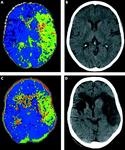

(A) Perfusion CT (time to peak (TTP) map) of acute left MCA ischaemia sub-three hours and (B) equivalent non-contrast CT. Perfusion CT predicts final infarct volume in the absence of arterial recanalisation: (C) three hour TTP map and (D) 24 hour non-contrast CT

Muir KW et al. Neuro 2005; 76: iii19-iii28; used with permission